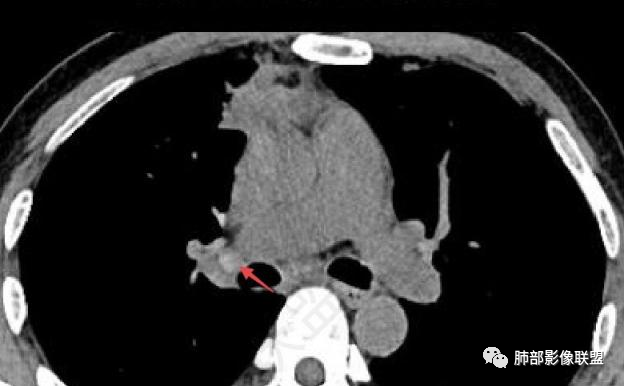

红箭-支气管分叉间条形高密度

2

这个脂肪间隙很模糊。

3

这里也是。还有血管增粗。

4

增大淋巴结

很多增大的淋巴结,强化方式一致均匀,

未见明确坏死,融合不明显,没有明确的分布优势。

5

这里是软组织密度,纵隔内突入

我觉得这里可以怀疑是栽桩。

肝脏病变明确,是轻度强化,延迟强化特点,边缘模糊,有轻微的包膜挛缩。